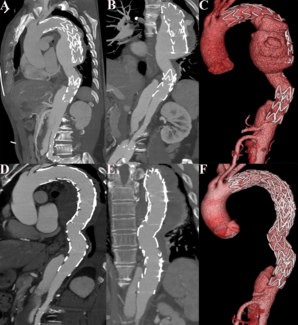

Leizhi Ku, MD; Di Huang, MD; Xiaojing Ma, PhD

A 67-year-old man was referred to our hospital because of stent leakage after thoracic endovascular aortic repair for type B aortic dissections 6 years ago. Computed tomographic angiography revealed distal stent graft-induced new entry with...